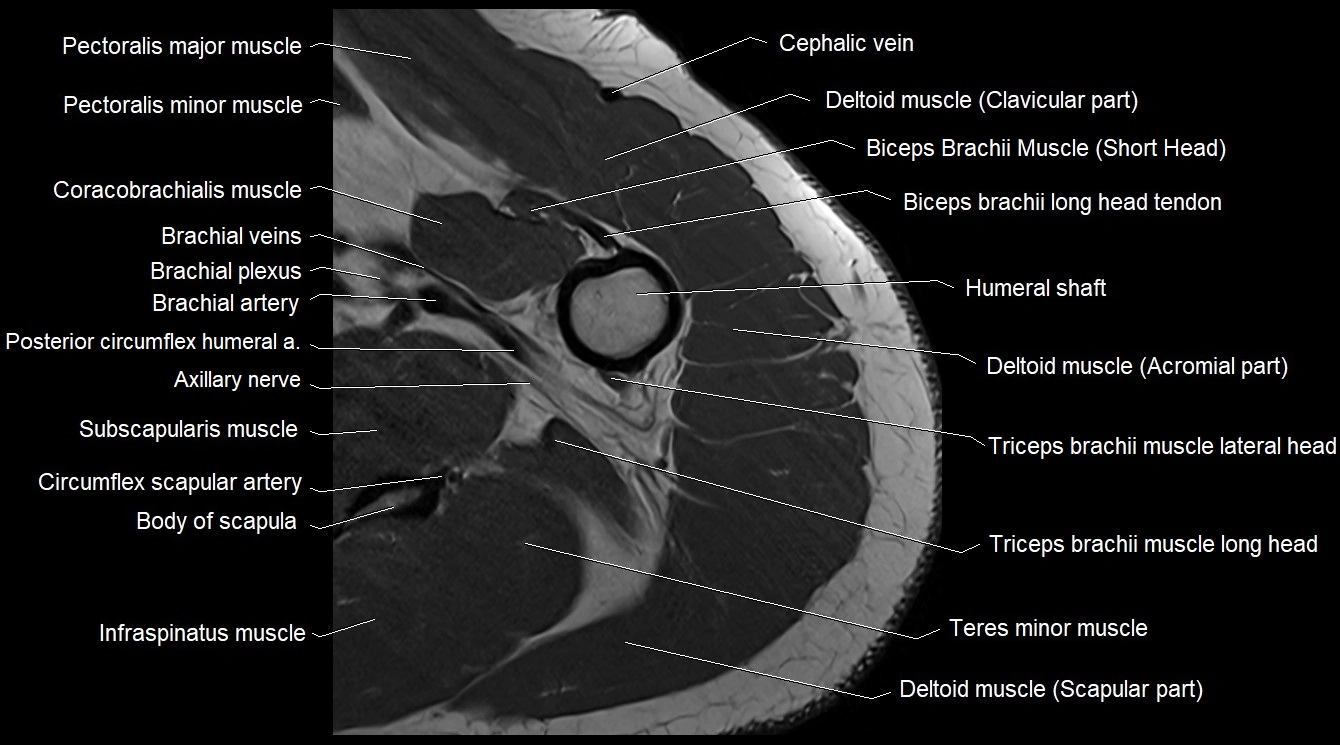

MRI image